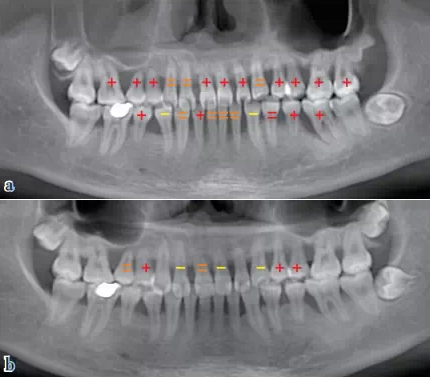

QQ圖片20150710154752.png圖7 放射影像評估:與初診比較,牙槽骨骨量和骨密度明顯增加,上頜竇炎癥得到控制、明顯減輕;與初診比,牙齒松動顯著好轉(zhuǎn)(“+”表示松動Ⅲ度,“=”表示松動Ⅱ度,“-”表示松動I度),(a)初診,(b)兩年后評估